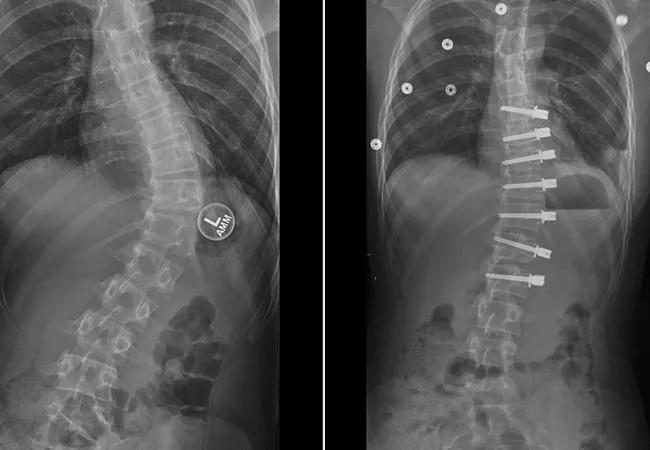

Feature image: 13-year-old female with progressive scoliosis treated with vertebral body tethering. Images show early correction from the preoperative posteroanterior x-ray and the patient’s first erect postoperative posteroanterior x-ray.

As this is a relatively new procedure, indications continue to evolve. The procedure is designed to be performed in children with growth remaining and idiopathic curvatures between 35 and 70°. Children who are near skeletal maturity based on a bone age film or iliac crest apophysis are not candidates for this procedure. Goals of the procedure include stabilization of the convex portion of the curve with non-fusion instrumentation, modest correction in the operating room and completion of the deformity correction with future remaining growth.

Recently, newer techniques have been developed to permit guided growth for growing patients with progressive scoliosis. These techniques were developed to stabilize the spine and allow remaining growth to occur. During the post-surgical growth, the deformity can correct slowly over time. This technique is similar to growth modulation techniques used in the lower extremities of children which have been commonplace for years. (i.e. stapling, physeal plating, epiphyseodesis). Vertebral body tethering is one such technique that permits continued growth without fusion and, as such, preserves motion.